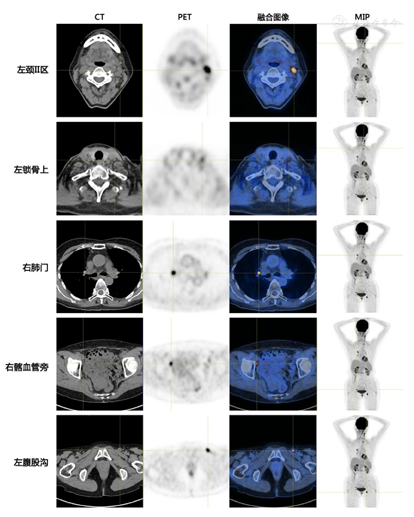

进一步行PET/CT检查(图1)示:1.双上颈、左侧锁骨上区、双侧髂血管旁、双腹股沟区多发淋巴结代谢活跃,炎性病变与淋巴瘤浸润鉴别。2.双肺多发斑片、条片及类结节影,部分代谢略活跃,右侧腋窝、纵隔、双肺门淋巴结代谢活跃/较活跃,结合病史,考虑炎性病变可能性大。因患者未携带外院报告,本次PET/CT检查未能与之前的检查结果对比。